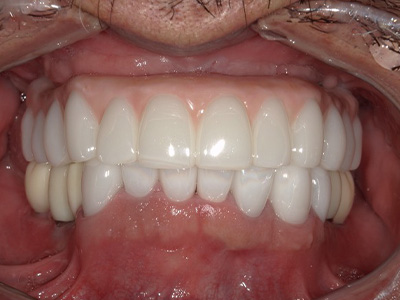

見た目も噛み心地も妥協しない

「補綴主導型インプラント」

一切妥協しないインプラント

最終的な被せ物(補綴)の理想的な形・位置から逆算し、インプラントを噛み心地と見た目に最適な位置に設計・埋入します。

技工士と院長が共同で設計し、その中心に正確にインプラントを配置。自然な見た目と快適な噛み心地の両立が可能になります。